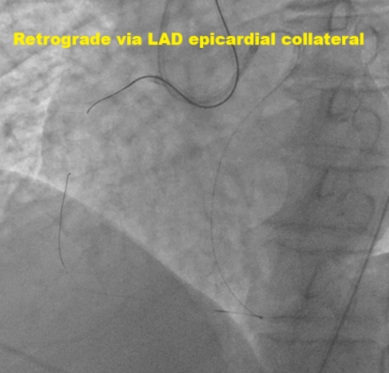

Dual access via right radial and femoral arteries. Failed to cross antegradely the proximal cap CTO using UltimateBros3 and Fielder XT-R guidewires / Corsair Pro, and retrogradely via septals collateral. Initially decided to abandon the procedure as deem small RCA vessel size. Unfortunately noted coronary perforation at proximal RCA CTO site, temporary tamponade with microcatheter. Retrograde Suoh3 wire via LAD epicardial collateral successfully crossed the distal cap of proximal RCA CTO, however, Caravel microcatheter unable to pass through the distal RCA branch for better support. Gladius EX14 guidewire supported with Corsair Pro microcatheter swiftly crossed the proximal cap antegradely (using the Suoh3 as the guide from retrograde) successfully till distal RCA branch. Caravel and Suoh3 removed retrogradely without complication. Predilate the RCA (prolonged balloon inflation) using SC 2.0x15mm (6-8atm, 3mins each) - to facilitate the plaque sealing of the perforation site. IVUS performed confirmed the wire in the true lumen. Stented with 2 overlapping DES 2.25x33mm (nominal) and 3.0x33mm (nominal). Noted the stent was from RCA-acute marginal branch, distal RCA was smaller vessel. Post-dilated distal stent with NC 2.5x15mm (nominal) while proximal stent with NC 3.0mm and NC 4.0mm. IVUS performed good stent apposition/expansion, with satisfactory MSA. Good angiographic result, TIMI 3 flow, no dissection/perforation noted. No pericardial effusion from echocardiography.

His hemodynamic was stable throughout the procedure. He was discharged from ward the next day. Clinical follow in clinic, he remained asymptomatic. Retrograde approach via the epicardial collateral remained a high risk route for PCI. Precaution to prevent untoward complication. This case demonstrated the salvage of the coronary perforation at RCA CTO via the LAD epicardial collateral.